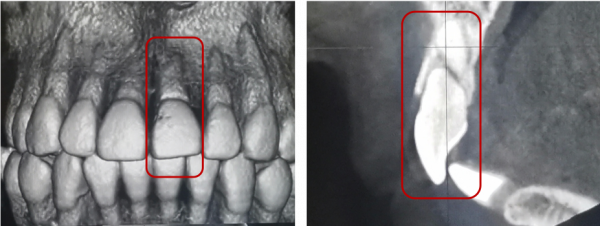

冠根折:累及牙釉質--牙本質--牙骨質折斷,累及牙釉質--牙本質--牙骨質--牙髓折斷

治療方案:方案(1)正畸或外科牽引4mm+冠延長+根管治療+樁核冠修復或根面覆蓋;方案(2)拔除患牙後種植修復;方案(3)意向性再植;方案(4)自體牙移植。